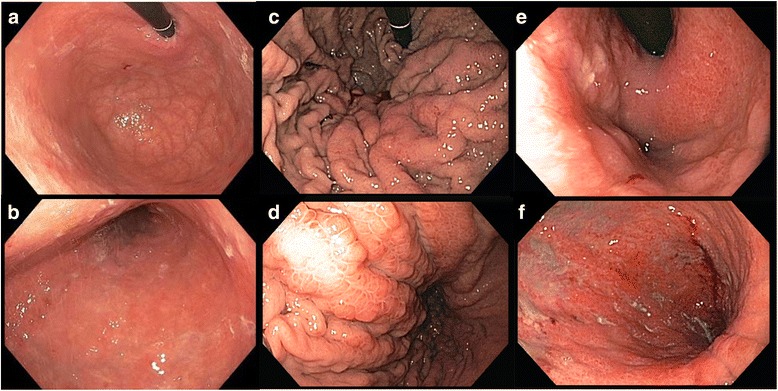

In regards to the quality of the mucosal involvement, two different subtypes of linitis plastica have been described (Fig. 3). In the first type, giant-fold or waffle-like, the mucosa demonstrates a characteristic morphological change consisting of an enhancement of the design of the folds, which remain flexible but appear prominent and crossing one another. This effect may be due to the relatively normal state of the mucosa in comparison to the involvement and contraction of the submucosal and muscular layers [2, 11]. The pattern of waffle-like LP has been extensively described in several Japanese studies, and in case reports of patients refusing surgery and subsequently being followed for years [11, 23–25]. The first lesion generally originates from the proximal or middle stomach, near the great curve, as a type IIc (flat depressed) early GC. This condition may remain stable for 2–5 years (slow-phase), until the lesion progresses to advanced GC and ulcerates reaching the submucosal layer. At this point, the ulcerative lesion can persist or heal, while the submucosal involvement, once a scirrhous reaction is initiated, enters a fast-phase, involving the entire stomach (LP) in about 1 year [23–25].

Fig. 3.

Endoscopic aspect of two different types of linitis plastica: the waffle-like (c, d) and the flat type (e, f). a, b The aspect of a normal stomach

In the second type, the flat type, submucosal involvement is paralleled by mucosal thickening or atrophy [11]. This type most commonly originates from the antrum, near the lesser curvature, and then extends to involve the antrum circumferentially. Flat type LP development has not been extensively studied. The difference between the characteristic mucosal pattern in waffle-like LP and the mucosal flattening and induration in flat type LP may due to diffusion of the neoplasm in a more superficial plane (involving the lamina propria, the muscolaris propria, or the mucosa itself) in flat type. The tumor is thought to originate near the pylorus, involve the antrum circumferentially, and extend to the entire stomach [9, 19, 27]. The flat type is commonly believed to be the most common in Western settings [11]. However, even if the original description by Brinton, most of the LP cases were identified as originating from the distal stomach, with hypertrophic mucosal folds [2], and a mixture of both subtypes [11]. In 1990, a US study demonstrated that up to 88% patients with scirrhous tumors present with the radiological features of thickened gastric folds. Moreover, in this study, 38% presented with mainly proximal involvement and 35% with mainly distal involvement [9]. Conversely, a 2004 Korean survey has reported a 22% rate of primarily proximal and a 59% rate of primarily distal involvement [12]. Therefore, the distinction between these two types is not clear-cut.